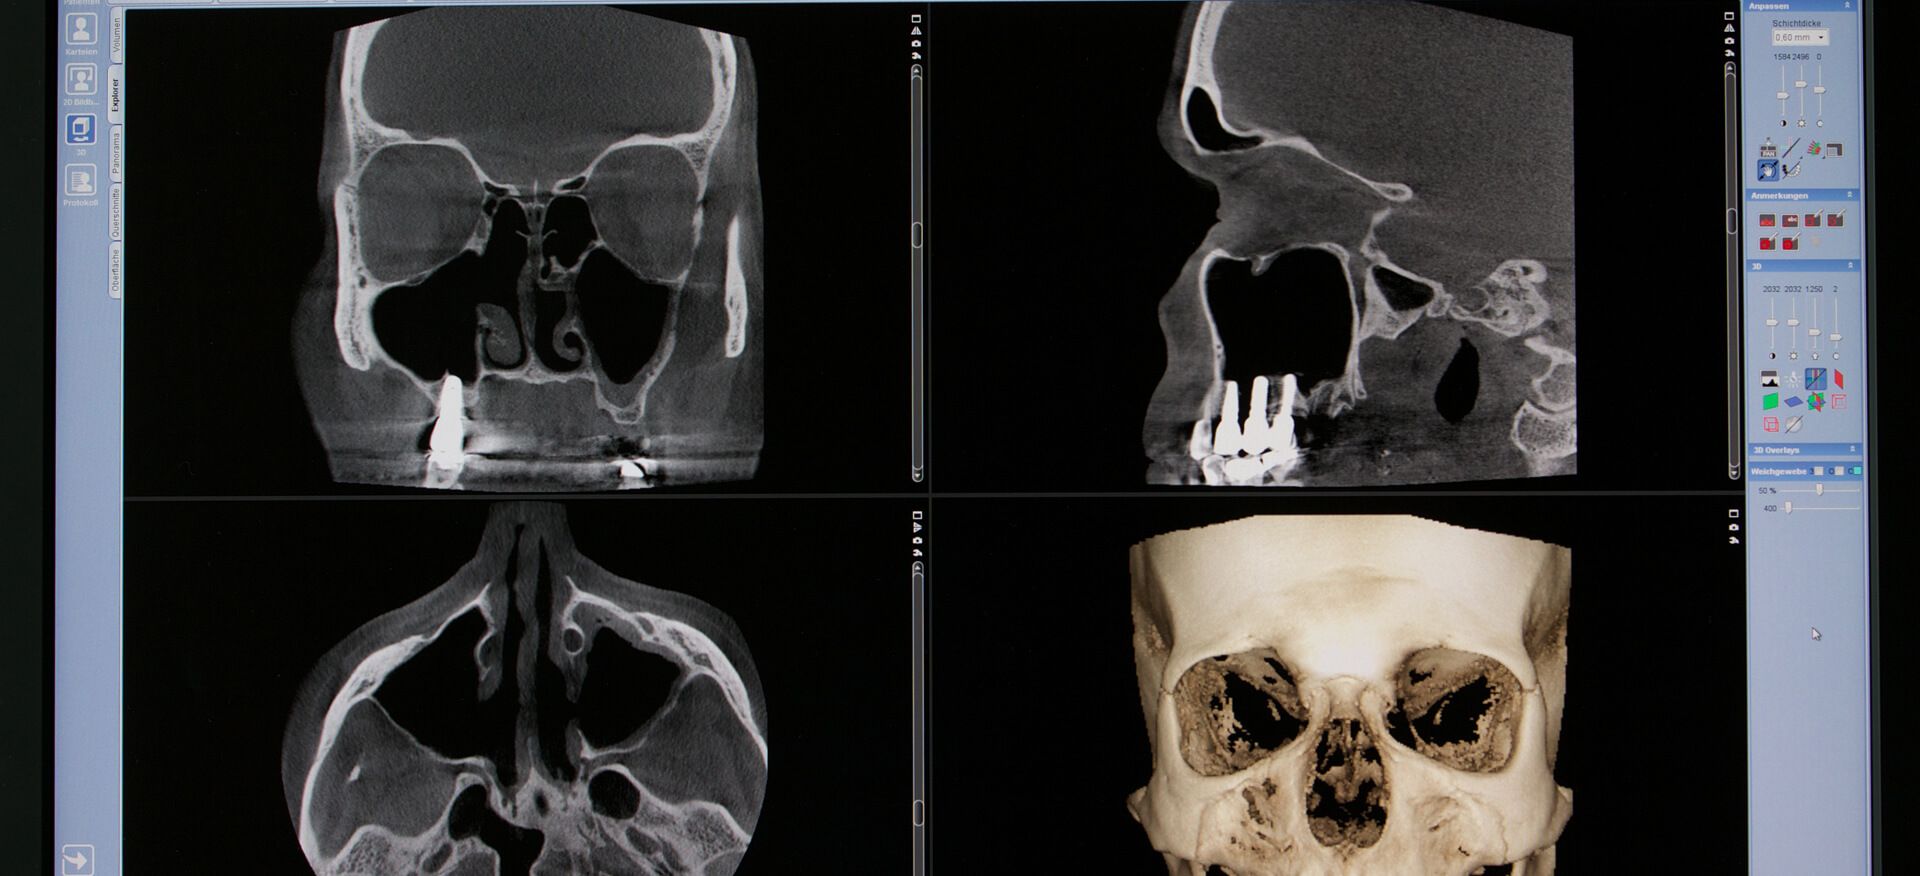

Digitale Volumentomographie (DVT):

Eine Besonderheit der HNO med. Nord sind bildgebende Untersuchungen mittels Digitaler Volumentomographie. Bei dieser Untersuchung können innerhalb weniger Sekunden dreidimensionale Aufnahmen des Schädels vorgenommen werden. Bezüglich Auflösungsvermögen und Genauigkeit ist die hochmoderne Digitale Volumentomographie der herkömmlichen Computertomographie überlegen, außerdem ist die Strahlenbelastung für den Patienten deutlich geringer. In der HNO-Heilkunde können mit Hilfe der DVT insbesondere Erkrankungen der Nasennebenhöhlen, des knöchernen Schädels (z.B. Knochenbrüche) und des Mittelohres sicher diagnostiziert werden.